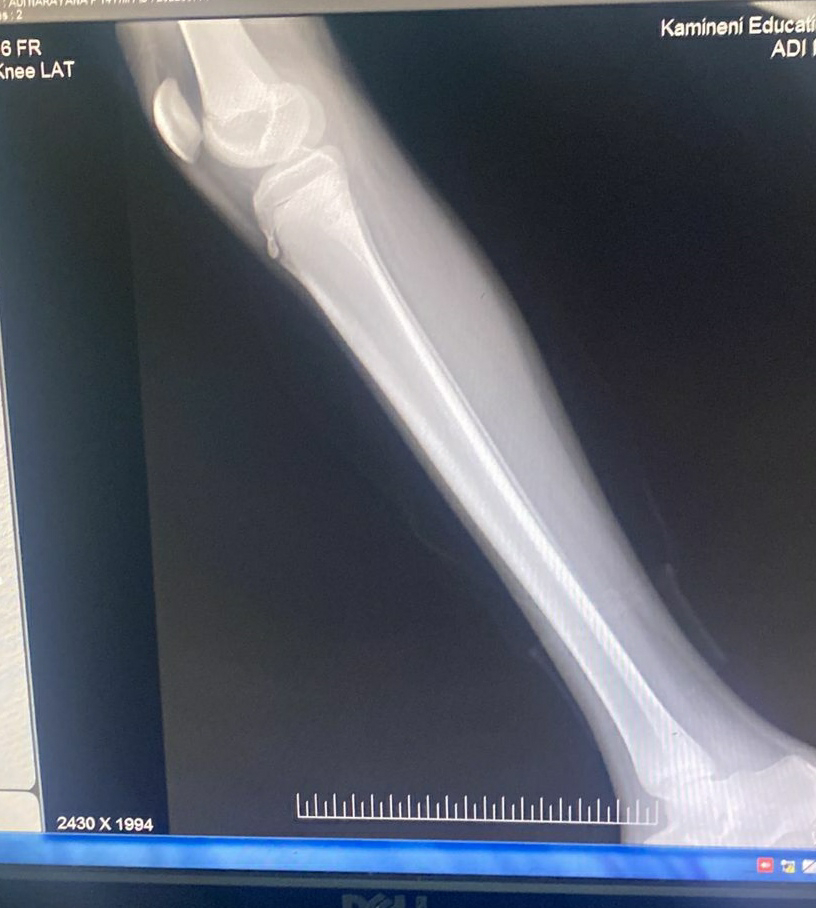

Xray 28/08/22